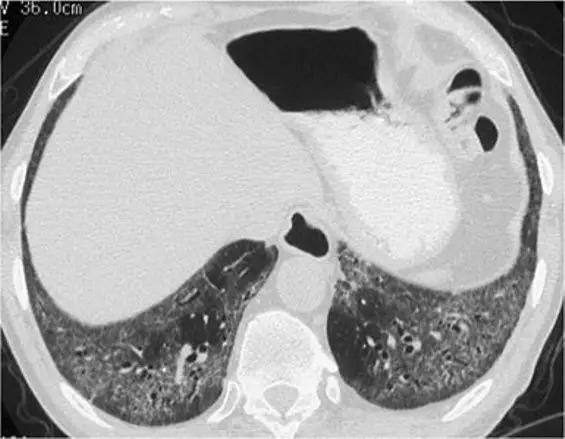

8、囊性病变

囊性模式由界限分明,圆形和外接空气的实质组成,有界限分明的壁和与正常肺。

经典疾病:淋巴管平滑肌肌瘤病(LAM),其特征是通常存在圆形的薄壁肺囊肿,没有在局部明显的特点,分布广泛,包括肋骨角和肺底。 LAM可能伴有胸水表现为胸膜胸腔积液。鉴别诊断是随机分布的囊肿,临床病史表现几乎只影响着育龄妇女。鉴别疾病:是肺组织细胞增生症、淋巴细胞性间质性肺炎(LIP)和小叶性肺气肿。

*LAM。上叶水平的HRCT表现出“囊性模式”,其特征是位于肺实质和隔中的许多大小不等的薄壁“真”囊腔的存在。

肺组织细胞增生症在处于纯囊性期(纯结节性和结节性-囊性期之后的第三期)时模拟LAM。它的特征是存在薄壁和厚壁的囊、形状呈异形,类似于苜蓿叶。囊肿具有特征性以上部和中部肺区分布为主。

*组织细胞增多症。上叶水平的HRCT揭示了一种“囊肿型”,其特征是许多薄或厚的“真”囊肿,形状奇异,大小不一。在右胸膜腔中发现引流导管以治疗气胸,这是这位27岁重度吸烟患者。